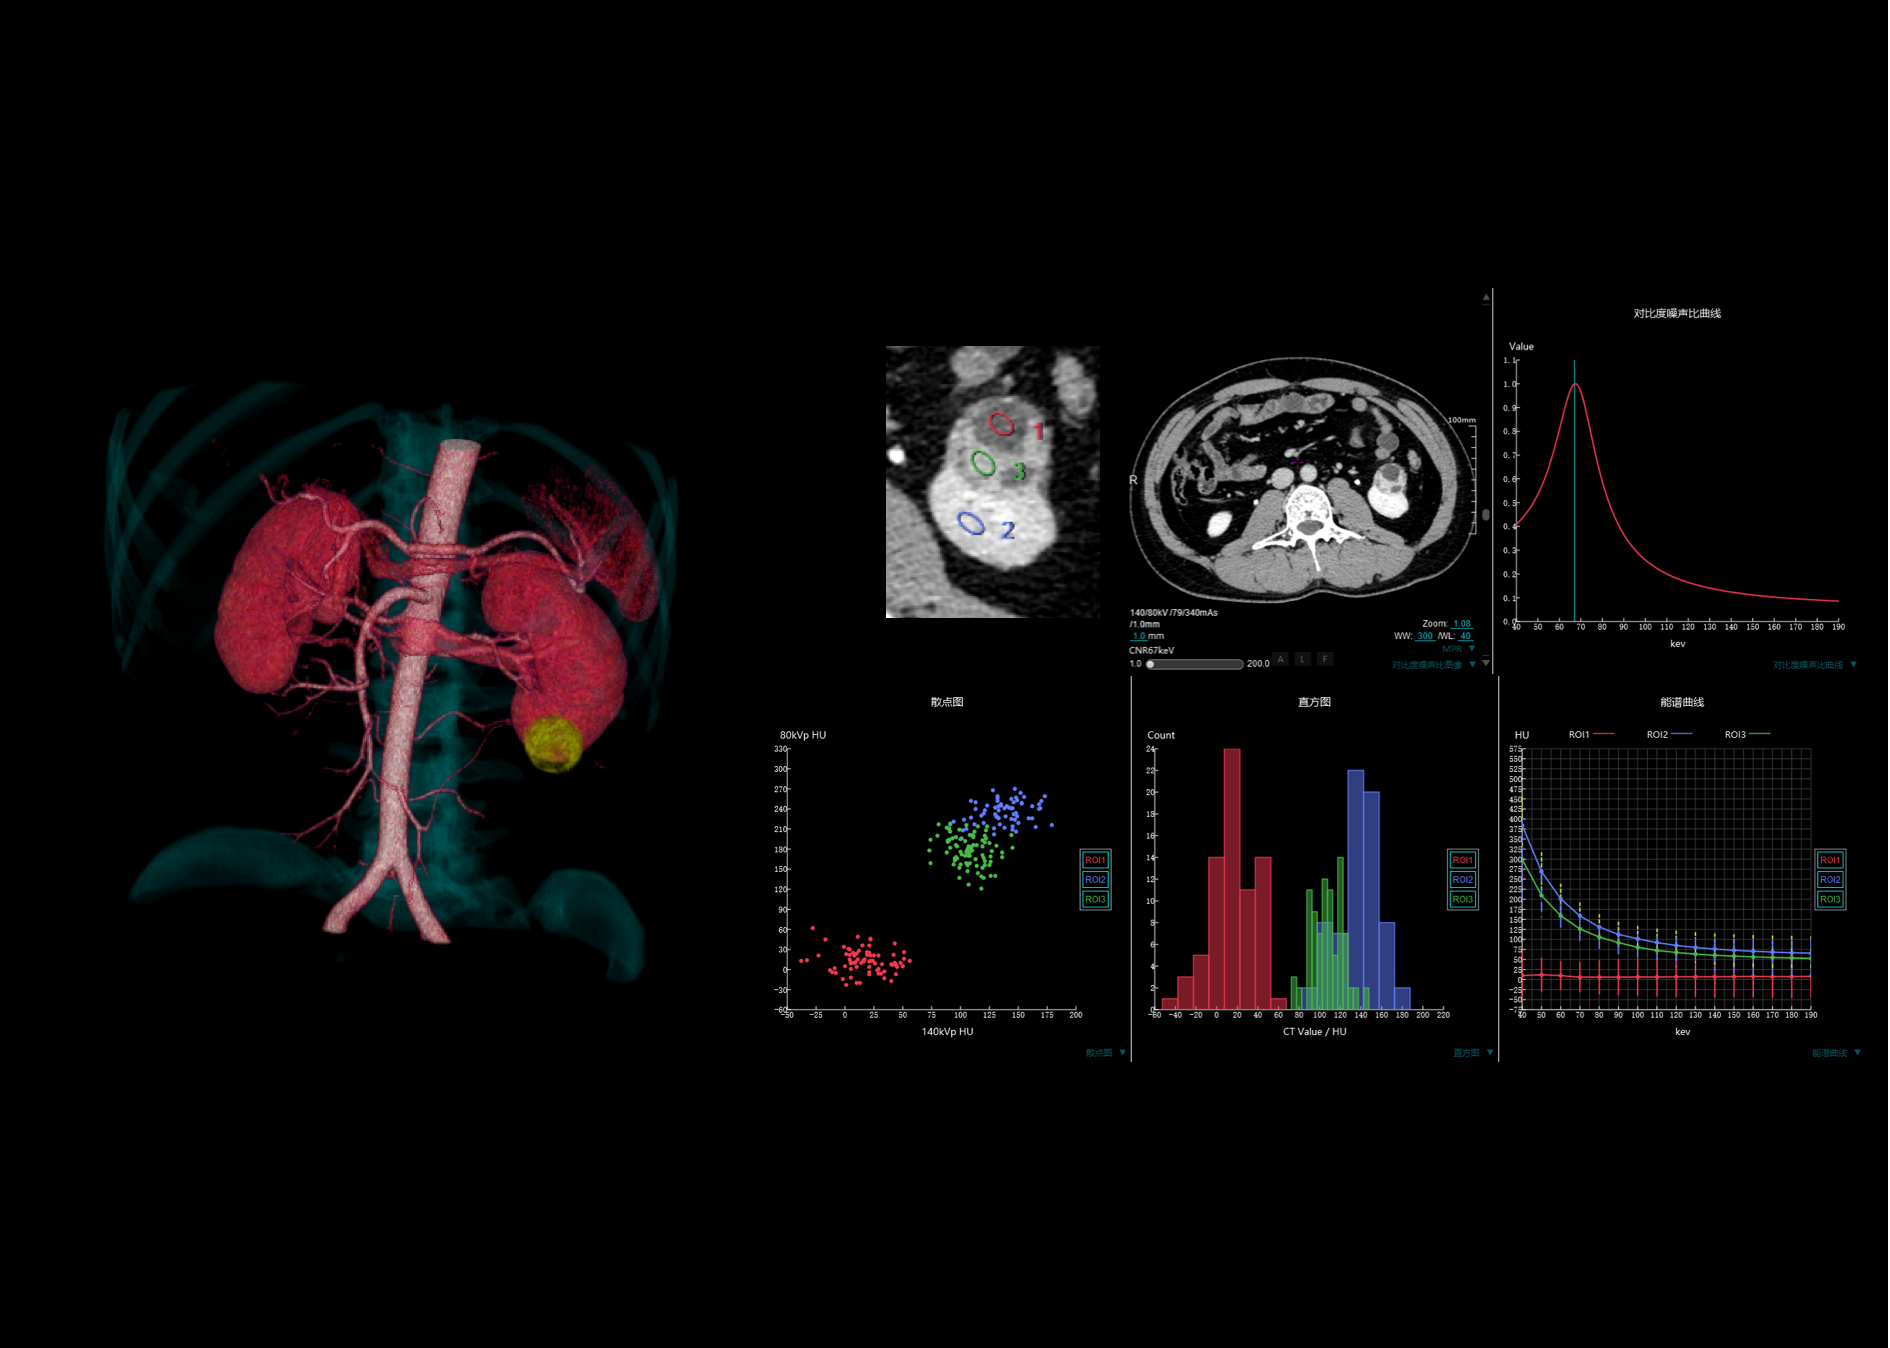

16厘米宽体能谱扫描,不动床轴扫覆盖单器官,获得组织中物质成分和能谱特征的定性及定量分析结果,为临床诊断提供更多可参考信息

用户可根据需求灵活设定准直宽度、采样间隔和剂量,优化患者辐射剂量。同时提供多种灌注协议,自动计算灌注参数